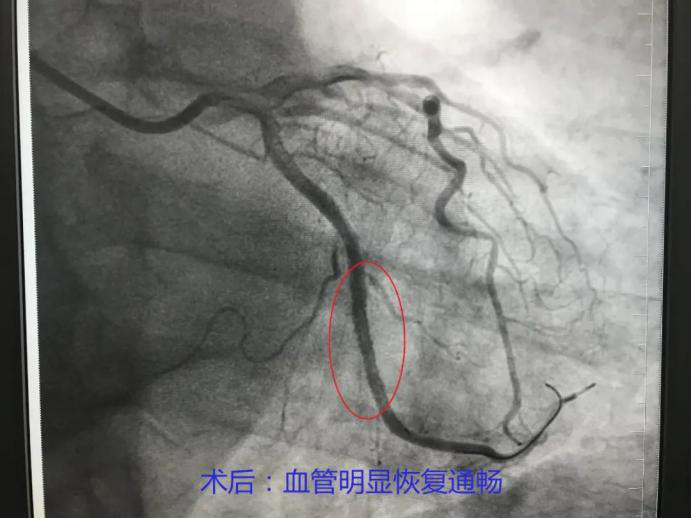

东南医院|上新台阶!重庆市东南医院首例心脏冠脉造影和心脏支架植入术成功开展

近年来 , 冠脉疾病逐年增高并呈年轻化趋势 , 经前期充分准备 , 重庆市东南医院心血管内科于7月22日成功开展3台冠脉造影、2台冠状动脉支架植入术 。 据悉 , 心脏介入手术在该院为首次开展 , 手术的成功标志着医院心血管内科介入技术迈上新台阶 。

冠状动脉造影可为冠心病诊断提供可靠的解剖和功能的信息 , 为评价预后、介入治疗或冠脉搭桥术方案的选择奠定了科学依据 , 是诊断冠心病的“金标准” 。

(术后前后对比)